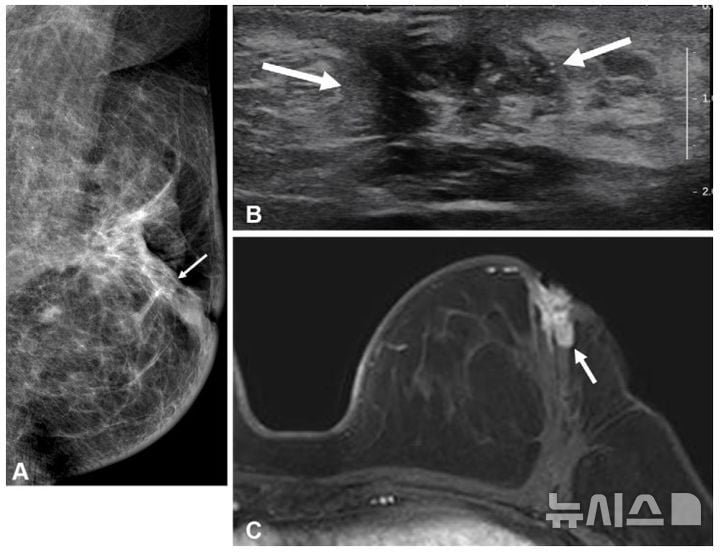

유방 MRI는 해부학적 해상력과 민감도가 높아, 기존 유방촬영술과 초음파로는 발견이 어려운 미세 종양까지 진단하는 첨단 영상 장비다. 연구팀은 전체 환자를 MRI 검사 경험 유무에 따라 구분한 뒤, 병기, 종양 크기 등 주요 임상 변수로 통계적 보정을 실시했다. 중앙 7.7년 추적 관찰 결과, 전체 재발률은 군별 차이가 없었으나, 수술 부위 내 국소 재발률은 MRI 검사군이 1.6%로, 비검사군(3.3%) 대비 절반 이하로 떨어졌다. 그 중 호르몬 수용체 음성 환자군에선 MRI 선별 시행이 동일 부위 재발 위험을 8.2%(MRI군) 대 20.7%(비MRI군)로 줄여 60% 이상 감소 효과를 보였다. 단, 호르몬 수용체 양성군에서는 유의한 차이는 확인되지 않았다.